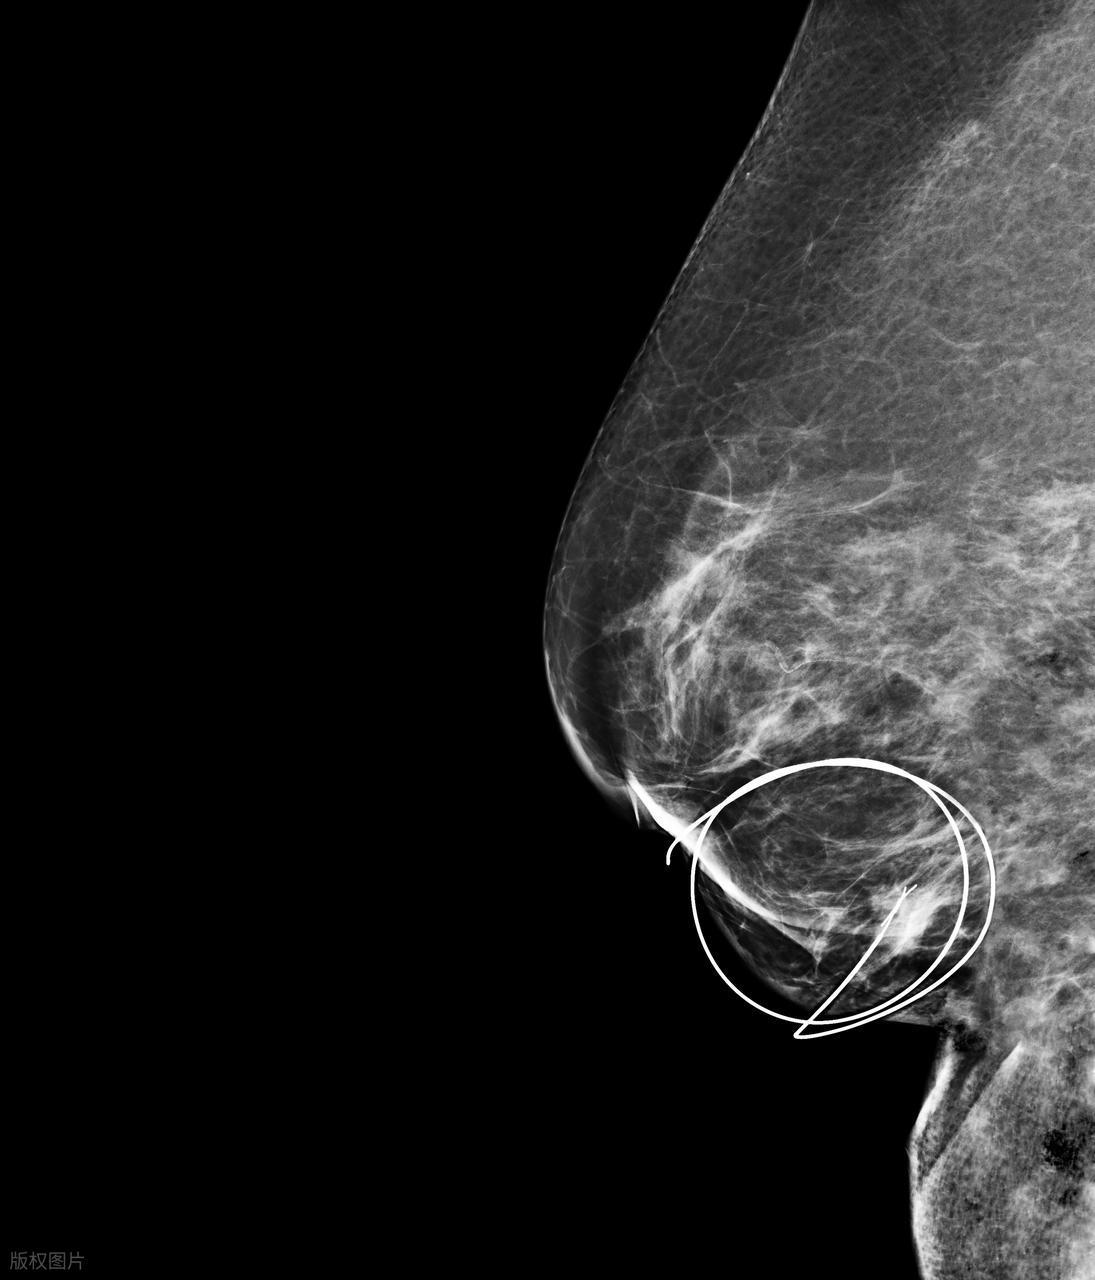

有些女性在日常生活中,會突然感覺到乳房某處有個堅實的“包塊”,但它不疼,摸不出波動感,也不會隨着生理週期變化。很多人以爲“不痛就沒事”,結果耽誤了檢查。事實上,乳腺癌早期常常表現爲邊緣不規則、質地偏硬、和周圍組織界限不清的無痛腫塊。一旦你或身邊好友發現類似異常,千萬不要“觀望”,及時向專業醫生反饋並安排乳腺彩超或鉬靶檢查。

定期體檢:30歲以上女性每年做一次乳腺彩超;40歲以上可加做鉬靶(X線)檢查。